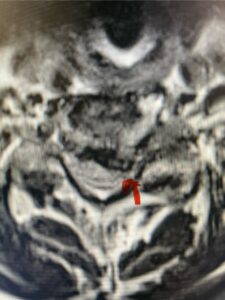

In this next case, this patient is a 47 year-old female who presents with intractable low back pain with severe pain, numbness, and weakness in the right lower extremity that had gotten progressively worse over a year. The patient had failed conservative management including physical therapy and epidurals. She was noted to have ⅘ weakness of plantar flexion. MRI demonstrated a large right L5-S1 disc herniation with severe compression of the descending right S1 nerve root (Fig 3). It was decided to perform a right L5-S1 hemilaminectomy for removal of the disc fragment and decompress the S1 nerve root. When you expose the disc, one must be certain to release any anterior adhesions to the nerve root in order to prevent a dural tear during retraction of the nerve root. It is also important to make sure during exposure and you finally encounter the dura after removing the ligamentum and fat, to make sure you are looking at the nerve root and not the main trunk of the thecal sac because if you don’t you can avulse or damage the nerve root if you retract the wrong structure.

Fig. 3a: Sagittal and axial T2-weighted lumbar MRI images demonstrating large right L5-S1 disc herniation (red arrows)

Fig. 3b

We found a massive subligamentous herniation which had to be revealed by having your partner retract the freed nerve root with a nerve root retractor and putting slight downward pressure on the more medial and anterior disc space. There is nothing more satisfying when the jelly (disc fragment) of the annulus (donut) comes squirting out and you remove a large chunk of disc material that clearly was stretching the ligament membrane and compressing the nerve root. This does cause back pain in addition to radiculopathy not only by the component of mechanical compression but also the stretching of the nerves within the ligament. We performed this surgery and noted that the nerve root was a very angry red color or hyperemic and we removed a large subligamentous fragment. The patient had improvement of her preoperative radicular symptoms.